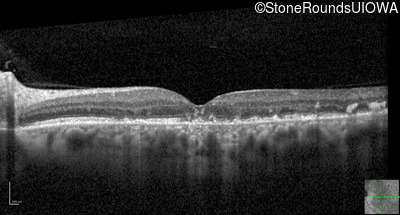

Optical Coherence Tomography - Left - 20/32 sc

Exemplar / OCT Stack